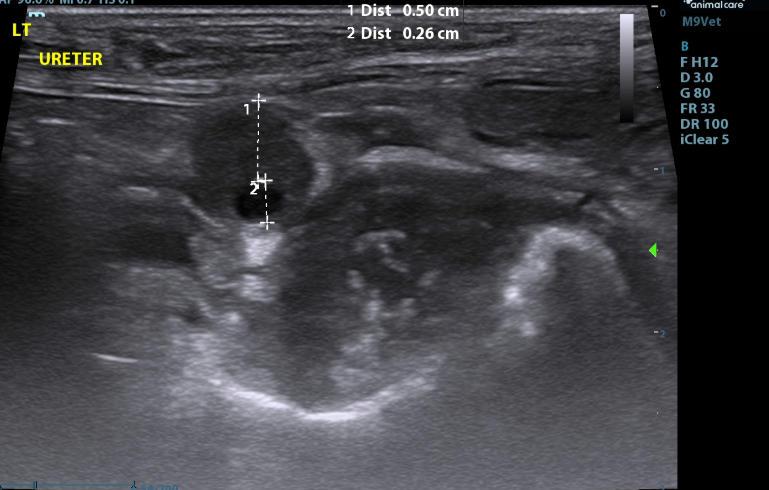

- Both ureters are mildly to moderately dilated along their length (Left - up to 4.3mm (decreased to 2.5mm at the level of the trigone); (Right up to 3.1mm - (decreased to 1.9mm at the level of the trigone)).

- The walls of the left ureter are mildly to severely and disproportionately thickened along its length (up to 5.0mm)